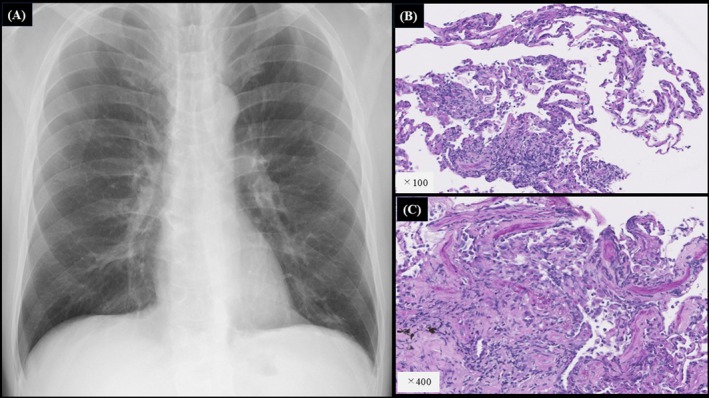

在全球范围内,梅毒病例一直在增加,并报告了肺部病变。然而,无症状的神经梅毒尚未被记录。这种情况往往不为人所知,其症状与其他传染性和非传染性肺部疾病相似。在被定义为梅毒的第二种形式的梅毒肺炎中,肌肉注射青霉素(2400万单位)仍然是治疗的金标准,预后良好。本文首次报道一例无症状性神经梅毒伴多发肺结节和臀部脂肪营养不良。如果快速血浆反应素(RPR)抗体滴度高且随访时RPR检测困难,可考虑脑脊液(CSF)检查以进一步评估无症状神经梅毒。本例RPR高表达(154 ruu),且由于患者工作性质(长途运输),短期随访困难。因此,采用脑脊液进行早期诊断和治疗。

Globally, syphilis cases have been increasing and pulmonary lesions have been reported. However, asymptomatic neurosyphilis has not been documented. This condition is often unrecognised and presents with symptoms similar to those of other infectious and non-infectious lung diseases. In syphilitic pneumonia, defined as a secondary form of syphilis, intramuscular injection of benzylpenicillin (24 million units) remains the gold standard for treatment, with a favourable prognosis. This report presents for the first time a case of asymptomatic neurosyphilis with multiple pulmonary nodules and buttock lipodystrophy. If rapid plasma reagin (RPR) antibody titres are high and RPR testing is difficult during follow-up, cerebrospinal fluid (CSF) examination may be considered for further evaluation of asymptomatic neurosyphilis. This case showed a high expression of RPR (154 R.U.) and given the nature of the patient's work (long-distance transportation), short-term follow-up was difficult. Therefore, CSF was performed to enable early diagnosis and treatment.